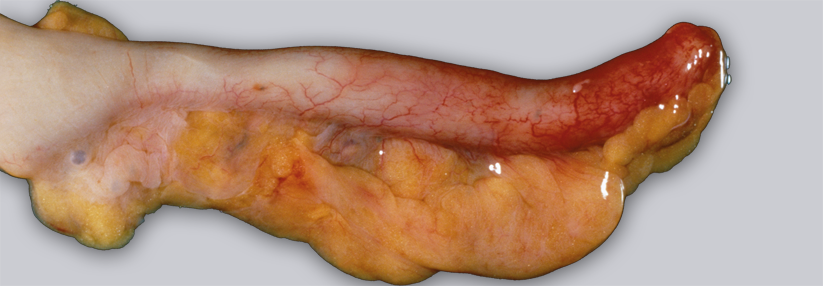

Bauchschmerzen sind das klassische Appendizitis-Symptom – was die Sache für den Arzt nicht einfacher macht. Denn Bauchschmerzen sind so unspezifisch, dass sie schnell auf die falsche Spur lenken. Ähnliches gilt für andere Zeichen, mit denen sich ein entzündeter Blinddarm meldet, etwa Verstopfungen, Übelkeit, Fieber und Durchfall. All das spielt eine maßgebliche Rolle dabei, dass bei 6 % der Erwachsenen und 4,4 % der Kinder die Wurmfortsatzentzündung in der Notfallambulanz zunächst nicht erkannt wird.

Überdurchschnittlich häufig, so ein Ergebnis der Untersuchung, erfolgte die Fehldiagnose bei Mädchen und Frauen. Auffallend oft waren zudem Patienten mit Begleit­erkrankungen betroffen. Dasselbe galt, wenn sich die Kranken mit der Symptomkombination Bauchschmerz und Verstopfung vorstellten. Alleiniger Bauchschmerz oder Abdominalschmerz plus Übelkeit schienen dagegen eindeutigere Hinweise zu liefern. Wurde bei Erstvorstellung ein CT angefertigt, stiegen die Chancen auf die richtige Diagnose. Wurde das Abdomen lediglich geröntgt, sanken sie. Was wohl damit zu tun hat, dass die Ärzte bei Anordnung der Tomographie schon den ganz konkreten Verdacht hatten, so die Vermutung der Autoren.